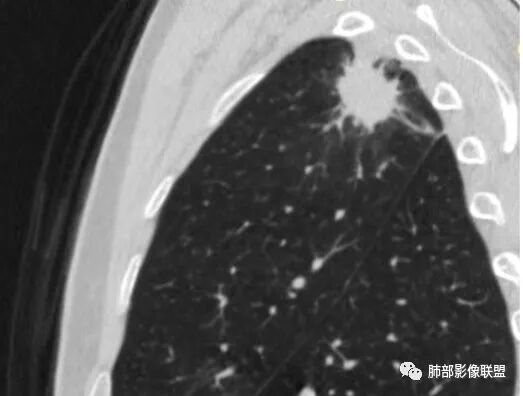

有栽赃吗?

这种属于宽基底与胸膜相连,附近胸膜增厚

栽赃是局部外侵犯

这里没有栽赃

如下图病例红色箭头的是典型栽赃:

南边 :

而该病例栽赃不明显,与增厚的胸膜分界比较清晰

下面这个病例这也是栽赃

边缘收缩均匀、U型凹陷、内有小点状钙化、桃尖征

支持炎性放前面、

不放心的是部分区域膨隆